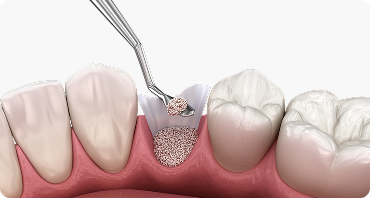

뼈이식 임플란트

임플란트에서 중요한 부분은 두꺼운 뼈와 건강한 잇몸에 있습니다.

뼈가 안 좋아 임플란트가 어려울 경우, 임플란트 식립을 위해

약해진 잇몸뼈를 이식하여 임플란트의 장기적인 수명을 향상시킵니다.

뼈이식 임플란트

성공적인 임플란트 식립을 위해서는 충분한 양과 질의 잇몸뼈가 필수적이지만,

경우에 따라 잇몸뼈가 부족한 경우가 있습니다.

이 경우 뼈이식술을 통해 먼저 잇몸뼈의 양과 질을 개선한 후

임플란트를 식립 해야 장기적인 안정성과 성공률을 높일 수 있습니다.

잇몸 뼈 소실 정도 진단

식립 할 위치에 인공뼈 이식

임플란트 식립 및 보철물 결합